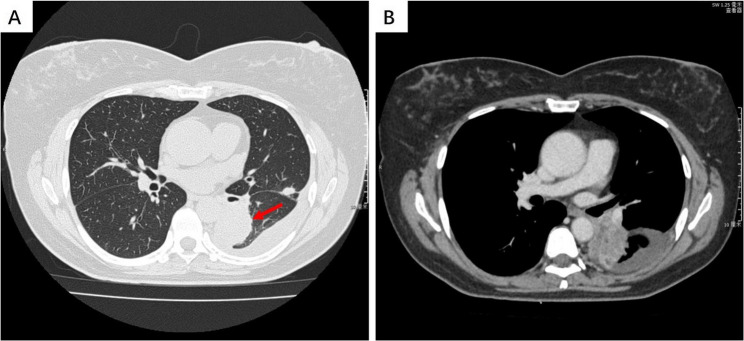

Case presentation: A 52-year-old woman presented with the complaints of persistent cough and dyspnea lasting for one week. Chest computed tomography demonstrated an irregularly shaped mass in the dorsal segment of the left lower lobe, accompanied with left pleural effusion and atelectasis. Cytological examination and cell block analysis revealed markedly atypical epithelial tumor cells exhibiting poor cohesion and rhabdoid morphological features. Immunocytochemical staining demonstrated positivity for Claudin4, TTF-1 and SMARCA4, while SMARCA2 expression was absent. Following these results, the pathological diagnosis was poorly differentiated lung adenocarcinoma with isolated SMARCA2 deficiency. Subsequently, next-generation sequencing (NGS) analysis identified a non-frameshift deletion in exon 19 of the EGFR gene. Based on these findings, target therapy with osimertinib was initiated, and the patient remained clinical stability for a duration of seven months following the initial presentation.